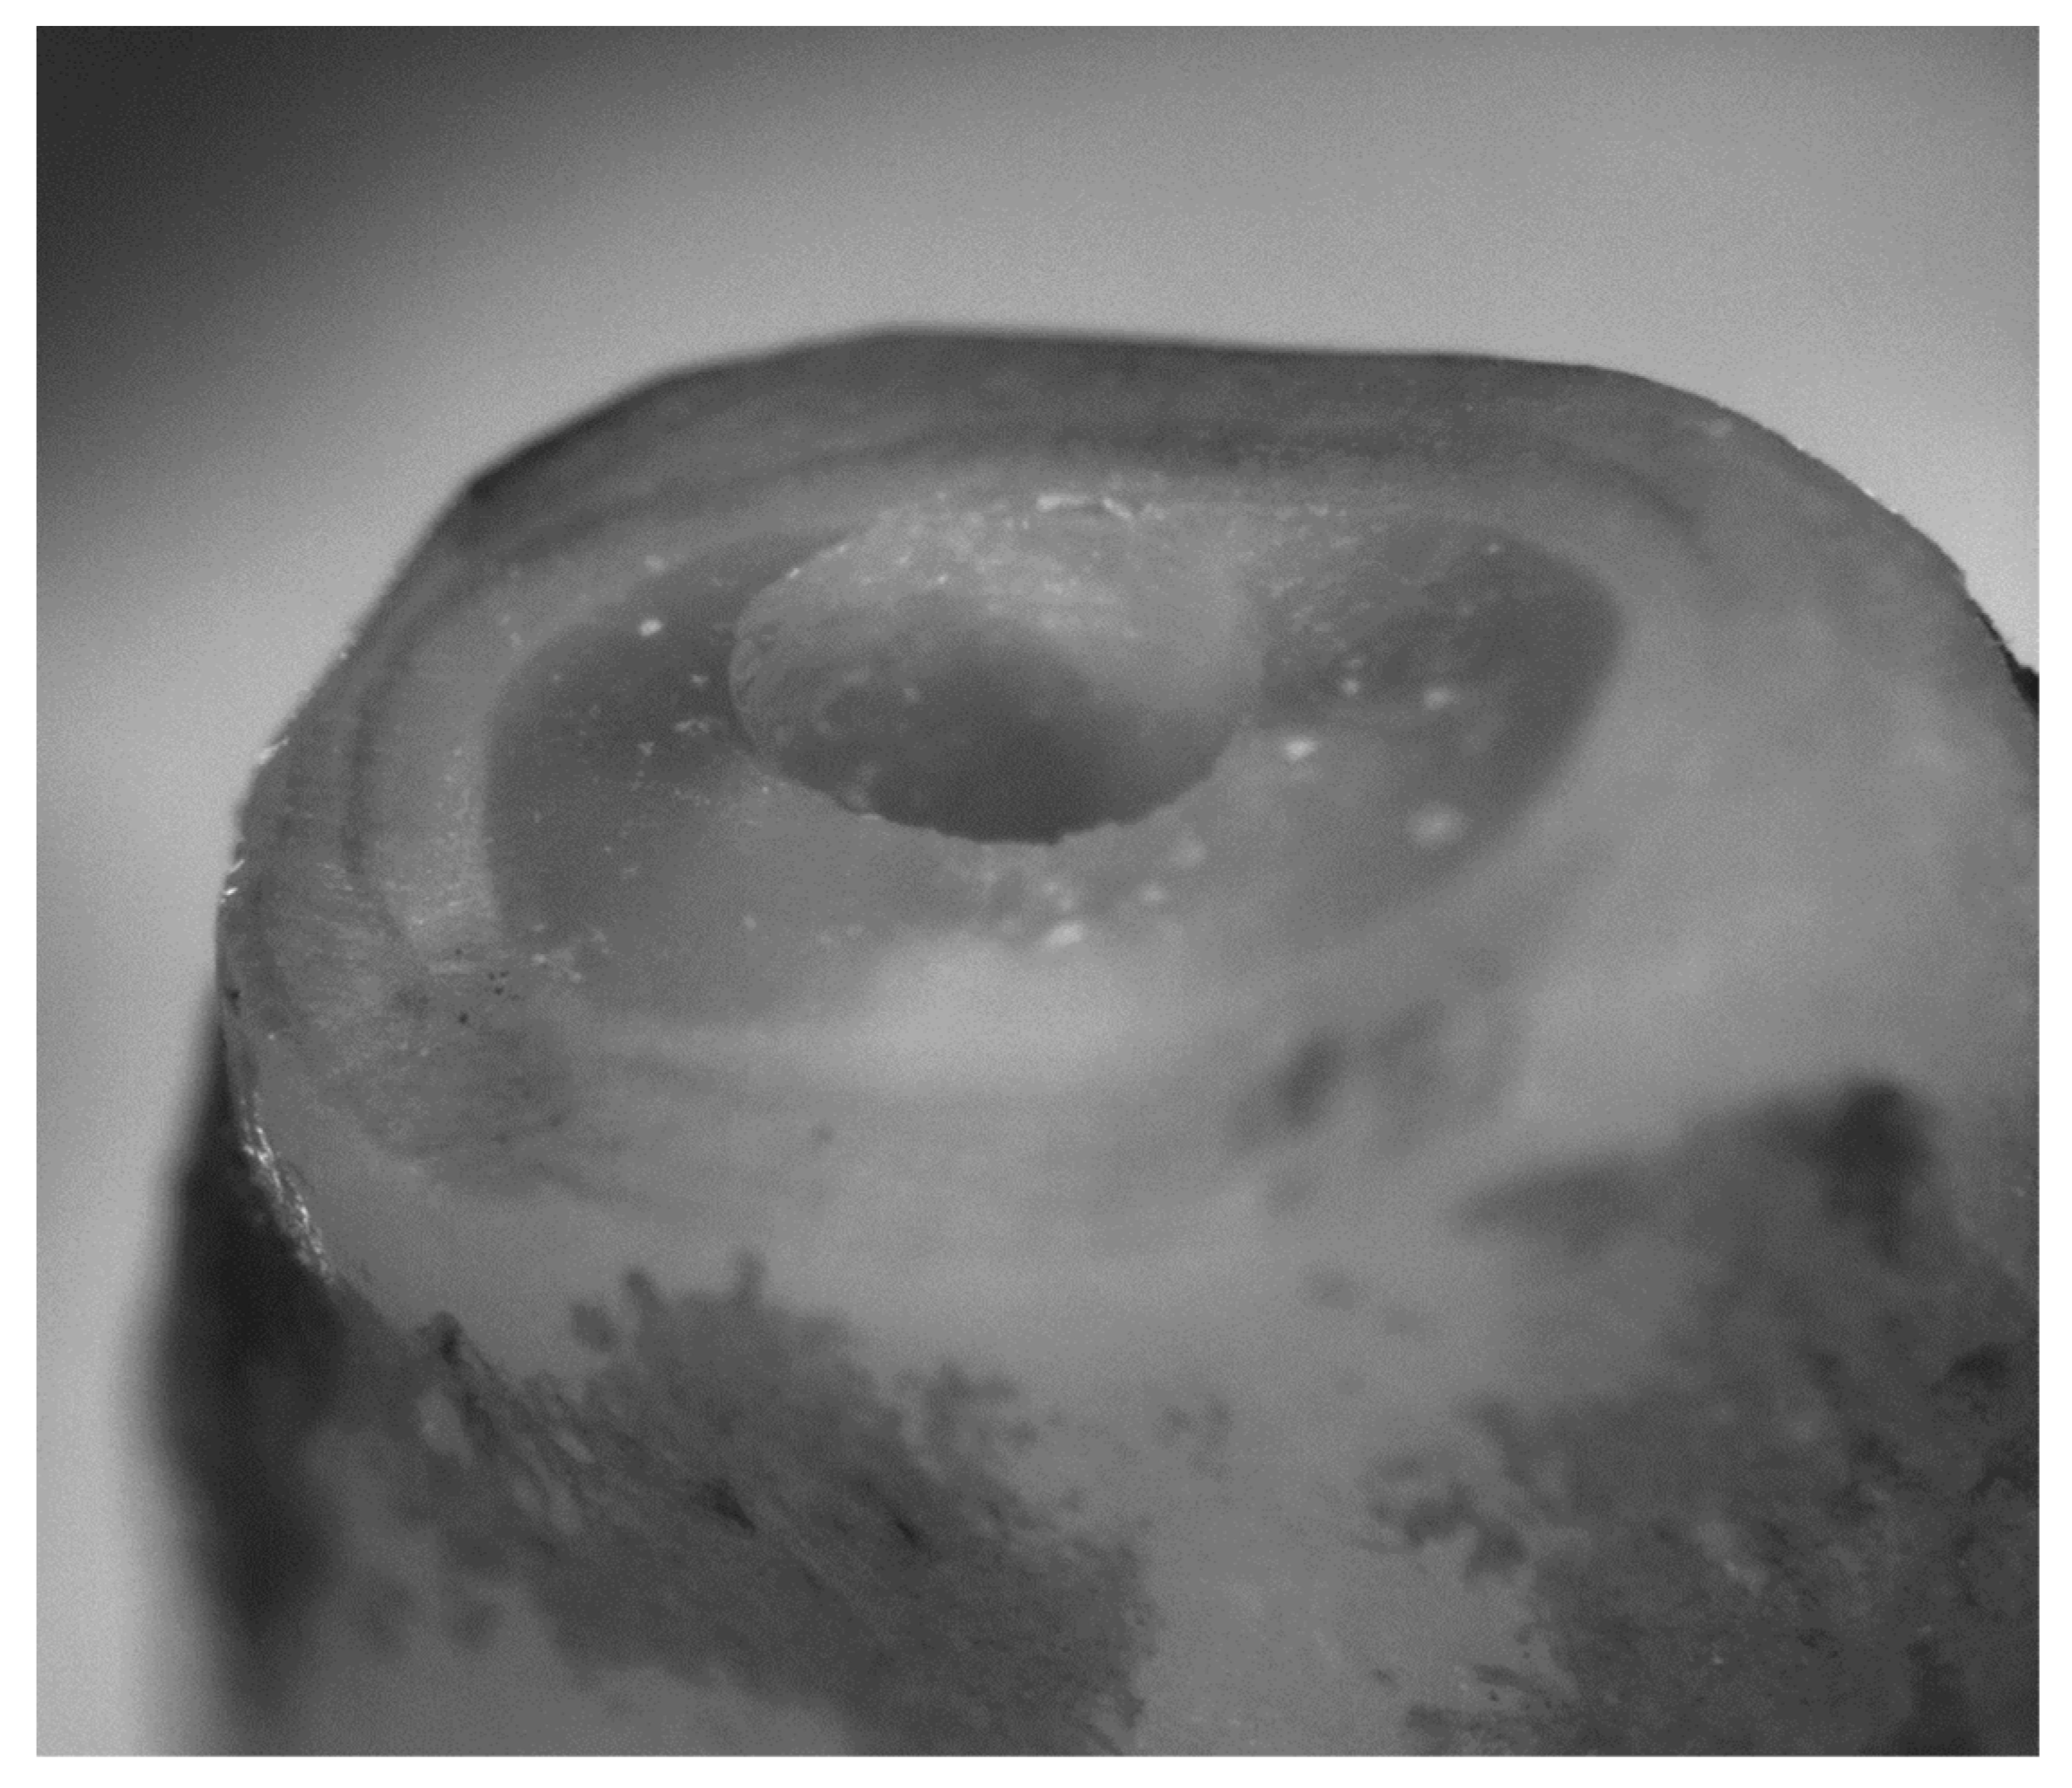

2.6. Retrograde Cavity Evaluation

3.3. Quality of the Retrograde Cavity